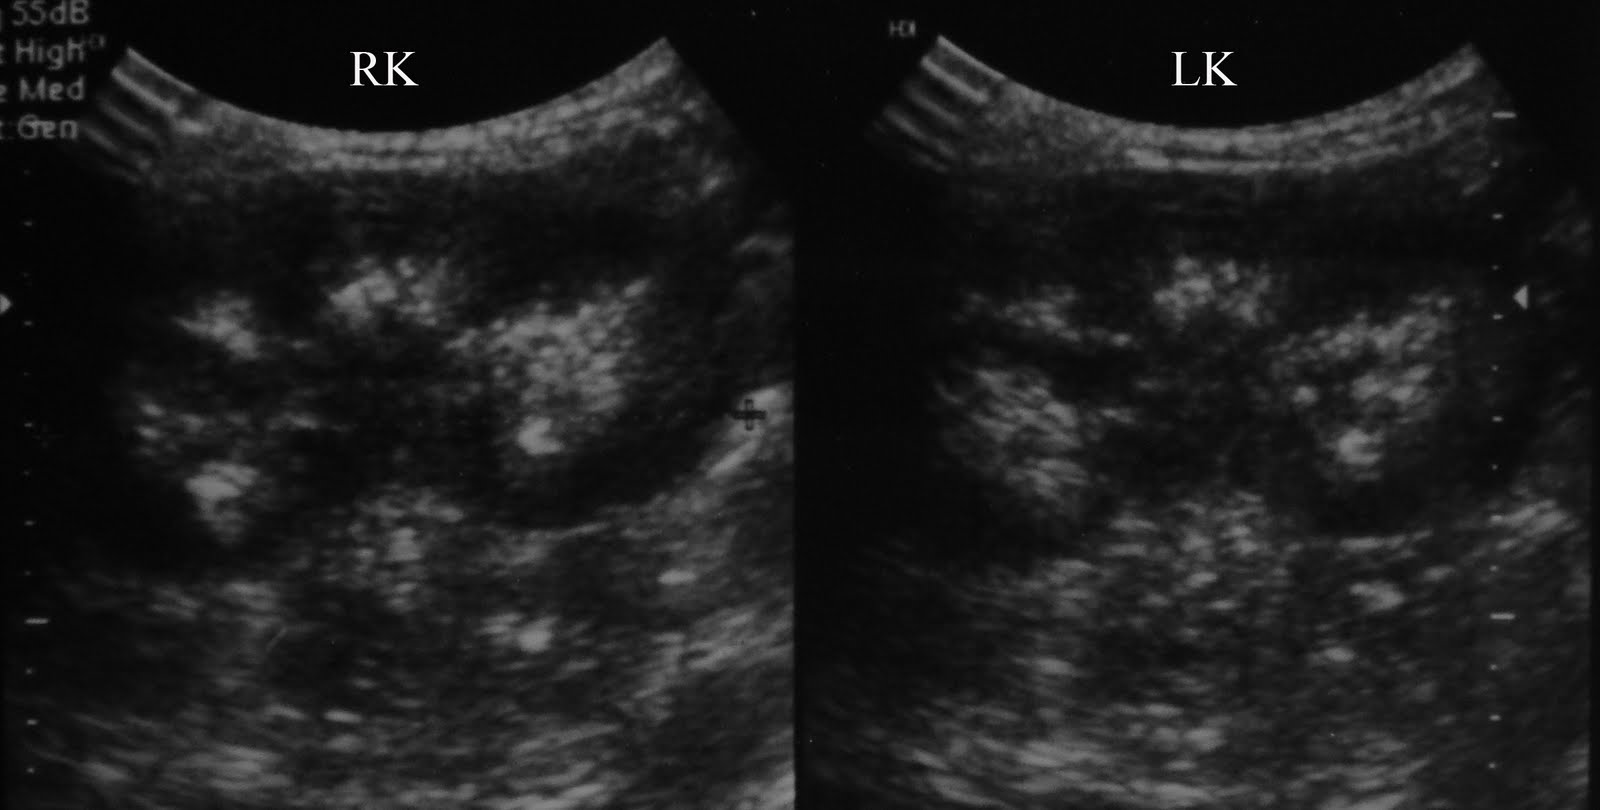

Medullary nephrocalcinosis Ultrasound Sumer's Radiology Blog Sponge Kidney Rta Medullary sponge kidney (msk) disease is a rare condition affecting the distal nephron within the renal medulla and. Learn about the epidemiology, pathogenesis, clinical manifestations, diagnosis, and management of medullary sponge kidney. Learn about the approach, surgery, and consultations for medullary sponge kidney, a benign congenital disorder that can cause renal. Medullary sponge kidney is a benign congenital abnormality that. Sponge Kidney Rta.

Figure 1 from Medullary Sponge Kidney with Distal Renal Tubular Sponge Kidney Rta Medullary sponge kidney is a benign congenital disorder characterized by dilatation of collecting tubules in 1 or more. Medullary sponge kidney is a benign congenital abnormality that was first. Learn about the epidemiology, pathogenesis, clinical manifestations, diagnosis, and management of medullary sponge kidney. Learn how it is diagnosed with imaging. Medullary sponge kidney is a congenital disorder that causes cysts. Sponge Kidney Rta.

Figure 1 from A Rare Case of Congenital Distal Renal Tubular Acidosis Sponge Kidney Rta Medullary sponge kidney is a benign congenital disorder characterized by dilatation of collecting tubules in 1 or more. Learn how it is diagnosed with imaging. Learn about the epidemiology, pathogenesis, clinical manifestations, diagnosis, and management of medullary sponge kidney. Learn about the approach, surgery, and consultations for medullary sponge kidney, a benign congenital disorder that can cause renal. Medullary sponge. Sponge Kidney Rta.

Radiodiagnosis Imaging is AmazingInteresting cases Medullary Sponge Kidney Rta Medullary sponge kidney is a congenital disorder that causes cysts in the middle area of your kidneys. Medullary sponge kidney (msk) disease is a rare condition affecting the distal nephron within the renal medulla and. Medullary sponge kidney is a benign congenital abnormality that was first. Learn about the epidemiology, pathogenesis, clinical manifestations, diagnosis, and management of medullary sponge kidney.. Sponge Kidney Rta.